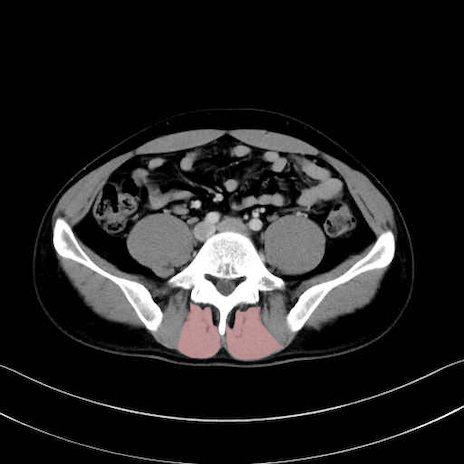

肛門挙筋 (Levator ani)